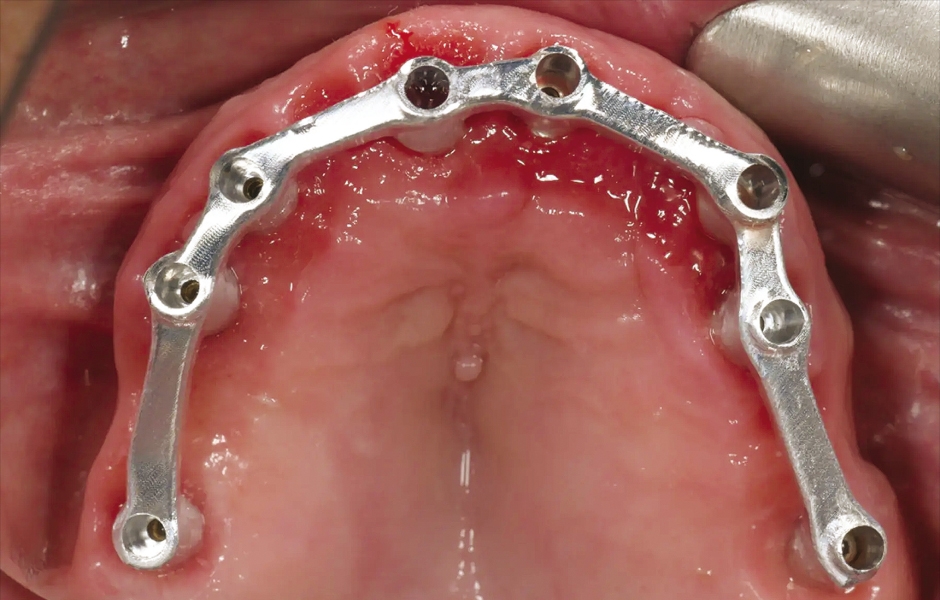

V den operace byla aplikována lokální anestezie a první chirurgická šablona byla stabilizována na zbývajících zubech k přípravě pěti fixačních pinů. Poškozené zuby byly extrahovány a druhá chirurgická šablona byla upevněna v připravených místech. Osm implantátů (Osstem TSIII SOI, Osstem Implant) bylo umístěno – pět do čerstvých extrakčních alveolů a tři do dříve zahojených oblastí. Všechny implantace proběhly plně navigovaně pomocí chirurgické šablony bez kovových pouzder a s dedikovanou chirurgickou sadou (OneGuide KIT, Osstem Implant; obr. 8). [11] Jeden implantát vyžadoval krestální sinus lift, který byl proveden plně navigovaným přístupem (OneCAS KIT, Osstem Implant; obr. 9). Xenogenní kostní materiál (A-Oss, Osstem Implant) byl použit k vyplnění extrakčních alveolů a dutiny sinu. [12] Na všechny implantáty byly okamžitě nasazeny multi-unit abutmenty a dočasné abutmenty (Osstem Implant) podle konceptu „one abutment, one time“. [13] Předem připravená dočasná protetika na bázi PMMA s kovovou výztuhou byla vložena a ihned fixována v ústech. V ordinaci byly provedeny úpravy pro dosažení správné okluze (obr. 10–12). Pacient obdržel pooperační instrukce a medikaci.

Obr. 6: Chirurgická šablona bez kovových pouzder pro přípravu fixačních pinů.

Obr. 8: Zavádění implantátu pomocí sady OneGuide KIT.

Obr. 9: Plně navigovaný krestální přístup do sinu pomocí sady OneCAS KIT.